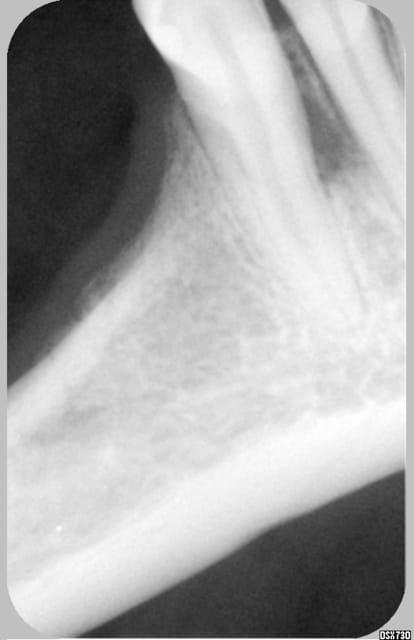

Patiente la cinquantaine, venue avec abcès en vestibulaire entre 33 et 32.

Stellite de 37 à 34 et de 47 à 45.

Lors du 2° rdv, plus de douleur, test au froid positif sur 33, 32, 31. Pas de réaction exploitable au chaud. Percution à peine plus sensible sur 32. Sondage normal autour des dents.

L'image montre une raréfaction osseuse entre 33 et 32.

t'as pas une radio plus precise de l'espace interdentaire ,une photo de bouche? les sepas des autres dents me paraissent un peu douteux tout de même .

Ton stellite il passe comment en lingual ? n'y a t il pas un rapport ?

C'est vrai qu'il y a atteinte du parodonte c'est evident mais ici il semble qu'il n'y ait pas de poches ( c'est ce que dit le roi de la gutta donc cela n'est pas comme ton cas. quelle est la cause? Le stellite comme je le pensais ?

Je maintiens, poche serpengineuse à point de départ lingual, d'autant plus que la connection métallique passe en face et appuye sur la gencive oedématiée à cet endroit avec effet de pompe pendant les fonctions,...